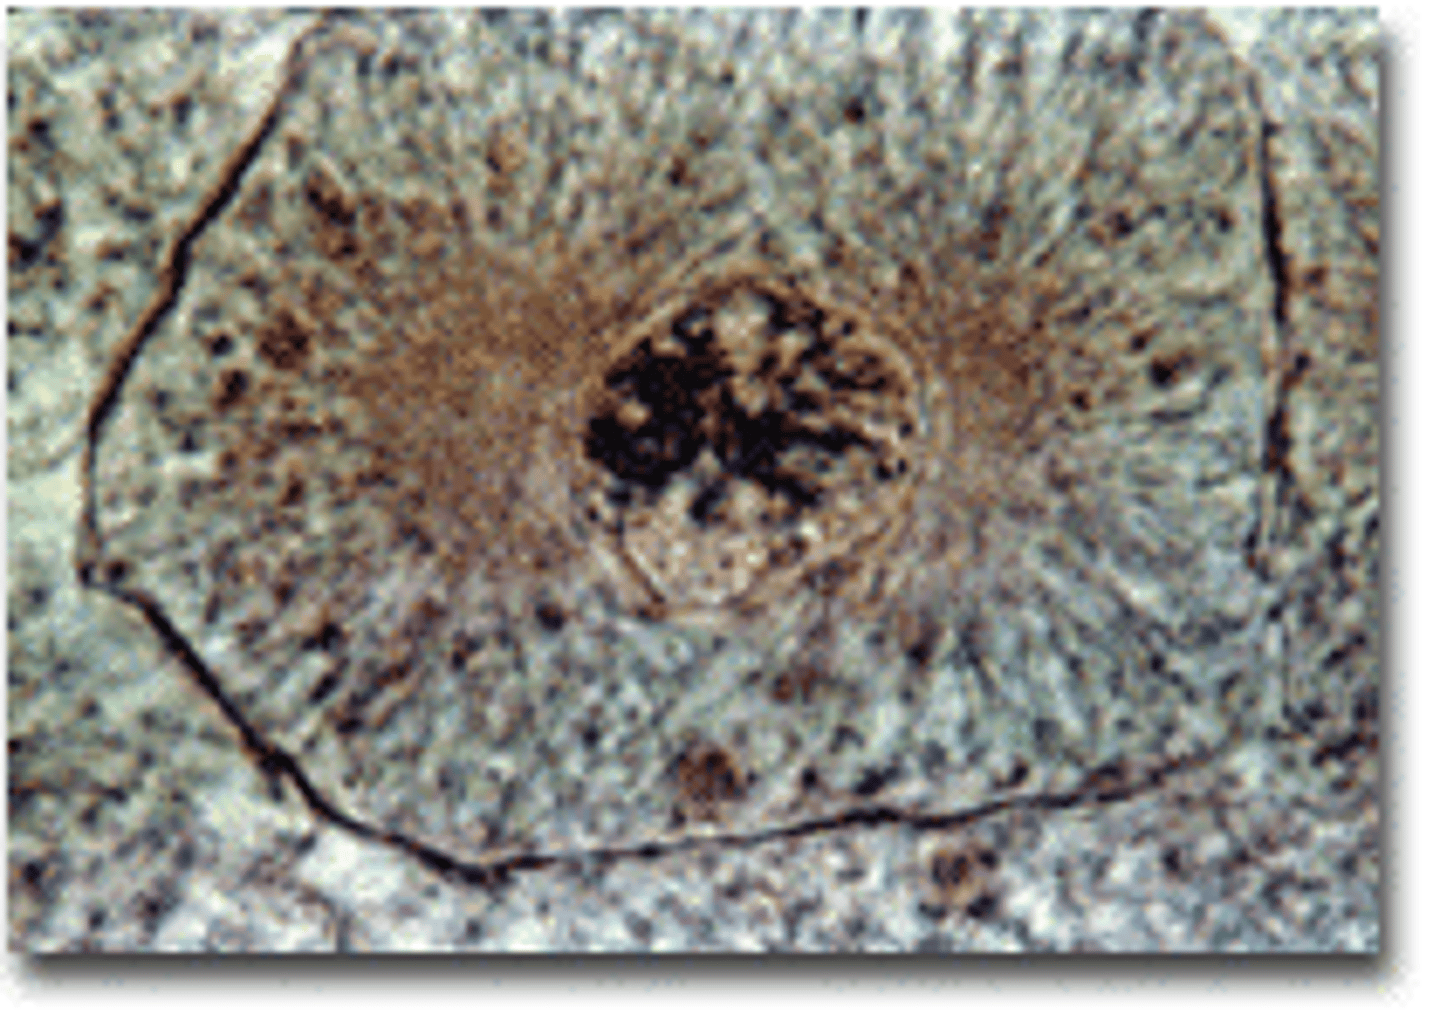

Prophase

Chromosomes become visable, nuclear envelop dissolves, spindle forms

Metaphase

Chromosomes line up in the middle of the cell

Mitosis

Process that ensures the transfer of a complete genome from a parent cell to two genetically identical daughter cells.

Part of eukaryotic cell division during which the cell nucleus divides. Plays a role in growth, tissue repair, and asexual reproduction.